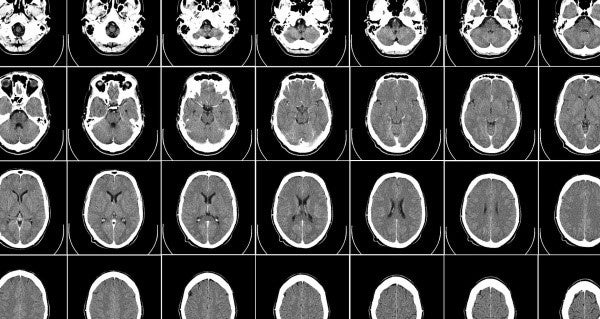

キングス カレッジ ロンドンの医用画像 AIの研究チームが、人間の脳のリアルな 3D 画像を AI で生成する手法を発見し、 10 万枚の脳の合成画像をヘルスケア分野の研究者に無償で公開することを発表しました。 このデータにより、 認知症やパーキンソン病をはじめ、 あらゆる種類の脳疾患への理解促進が期待されるます。

これらの画像は、合成データ(https://blogs.nvidia.com/blog/2021/06/08/what-is-synthetic-data/ )におけるヘルスケアの一分野の台頭を表しており、この種の合成データはすでにコンシューマー向け、ビジネス向けアプリケーション用コンピューター ビジョンの分野で広く採用されているものです。皮肉なのは、それらの分野では何百万枚もの実世界の画像が含まれたオープン データセットにもアクセスできることでしょう。

シミュレーションの結果とはいえ、検証を重ねたアルゴリズムに基づくそれらの画像は有用で、その見た目と働きはまるで本物の脳のようです。